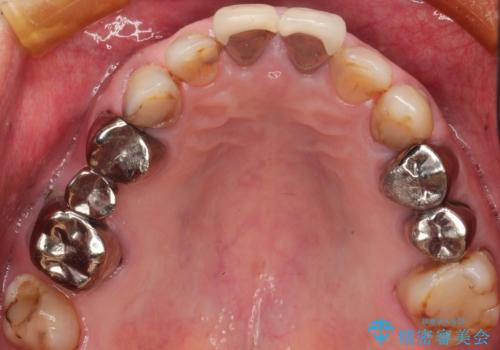

下顎の両側の奥歯が欠損しており、入れ歯をお持ちでしたが、うまく咬めずにほとんど使用していない状態でした。

上顎は全体的にクラウンの入れ替えと、下顎はインプラントの提案もしましたが、希望されなかったのでノンクラスプデンチャーの製作をする治療計画としました。